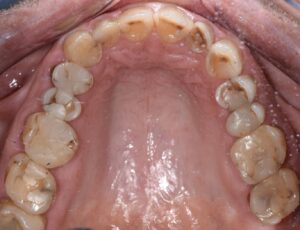

En typisk mun efter 30 år med komposit. Patienten lider av food impaction och är trött på att få göra om fyllningar varje år. Bild: Johan Hagman

Med Bioclear metoden – anatomiskt korrekt restauration utan kompositöverskott eller food impaction Bild: Johan Hagman